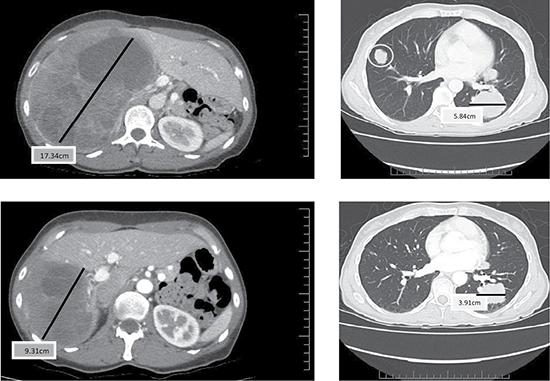

Partial responses by Response Evaluation Criteria in Solid Tumors (RECIST) were observed in two patients. These responses were not immediate. One patient had a decrease in the size of lung nodules achieving a partial response (PR) at cycle 8 and the other patient experienced reduction in size and number of liver and lung lesions achieving a PR by cycle 10 (Figure 1). One of the patients with PR had surgery and radiation as prior therapies and the other patient with PR also received surgery, radiation and one systemic chemotherapy prior to enrolling in this trial. While stable disease (SD) was the best response in 27 patients, 20 patients demonstrated a decrease in the size of their tumors (Figure 2). Another patient had improvement in ascites from cycle 6 through cycle 20 (minor response). The overall response rate (RR) was 7% with a clinical benefit rate (PR+SD) of 97% (Table 2). Anecdotal improvement in symptoms was also noted in 3 patients despite SD by RECIST. Three patients received extensive therapy to 56, 62 and 66 cycles.

Figure 1: Baseline (top) and Cycle 13 (bottom) computer tomography (CT) scan (chest and abdomen) from a patient who had a partial response and a duration of 7.2 months.